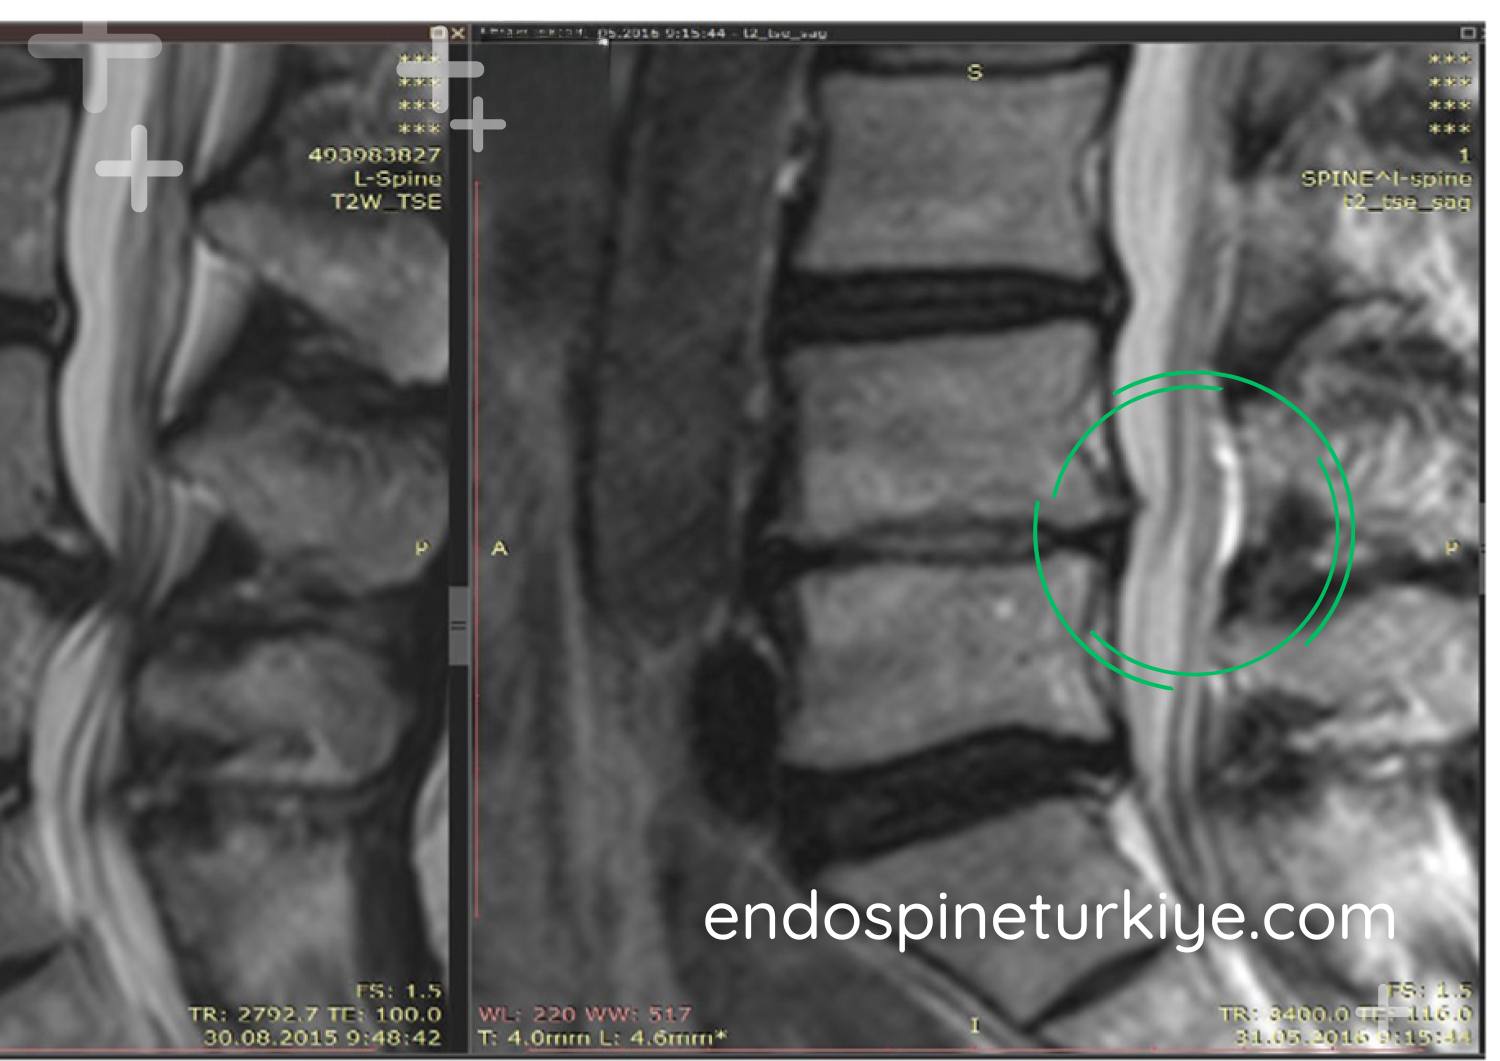

Bel fıtığı tedavi öncesi MR görüntüsü - L4-L5 disk hernisi

Tedavi Öncesi

Disk basıncı yüksek

Lazerle bel fıtığı tedavisi sonrası MR görüntüsü - PLDD sonucu

Tedavi Sonrası

Basınç normale döndü